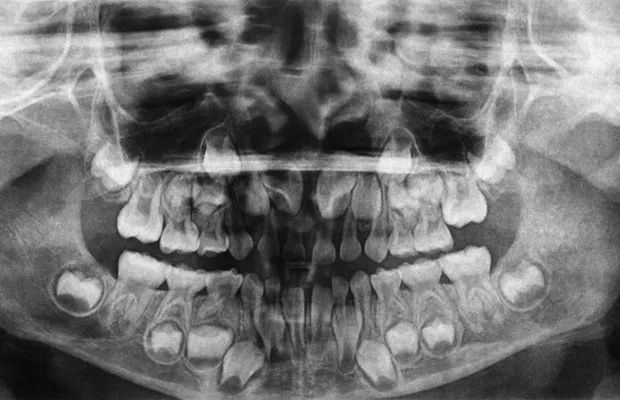

看了下换牙期小孩的牙片,嚯,乍一看有点吓人有木有。

@health24.com

其实,这是小朋友的恒牙埋在牙龈里,慢慢往上顶,之后就要把乳牙顶出去了。